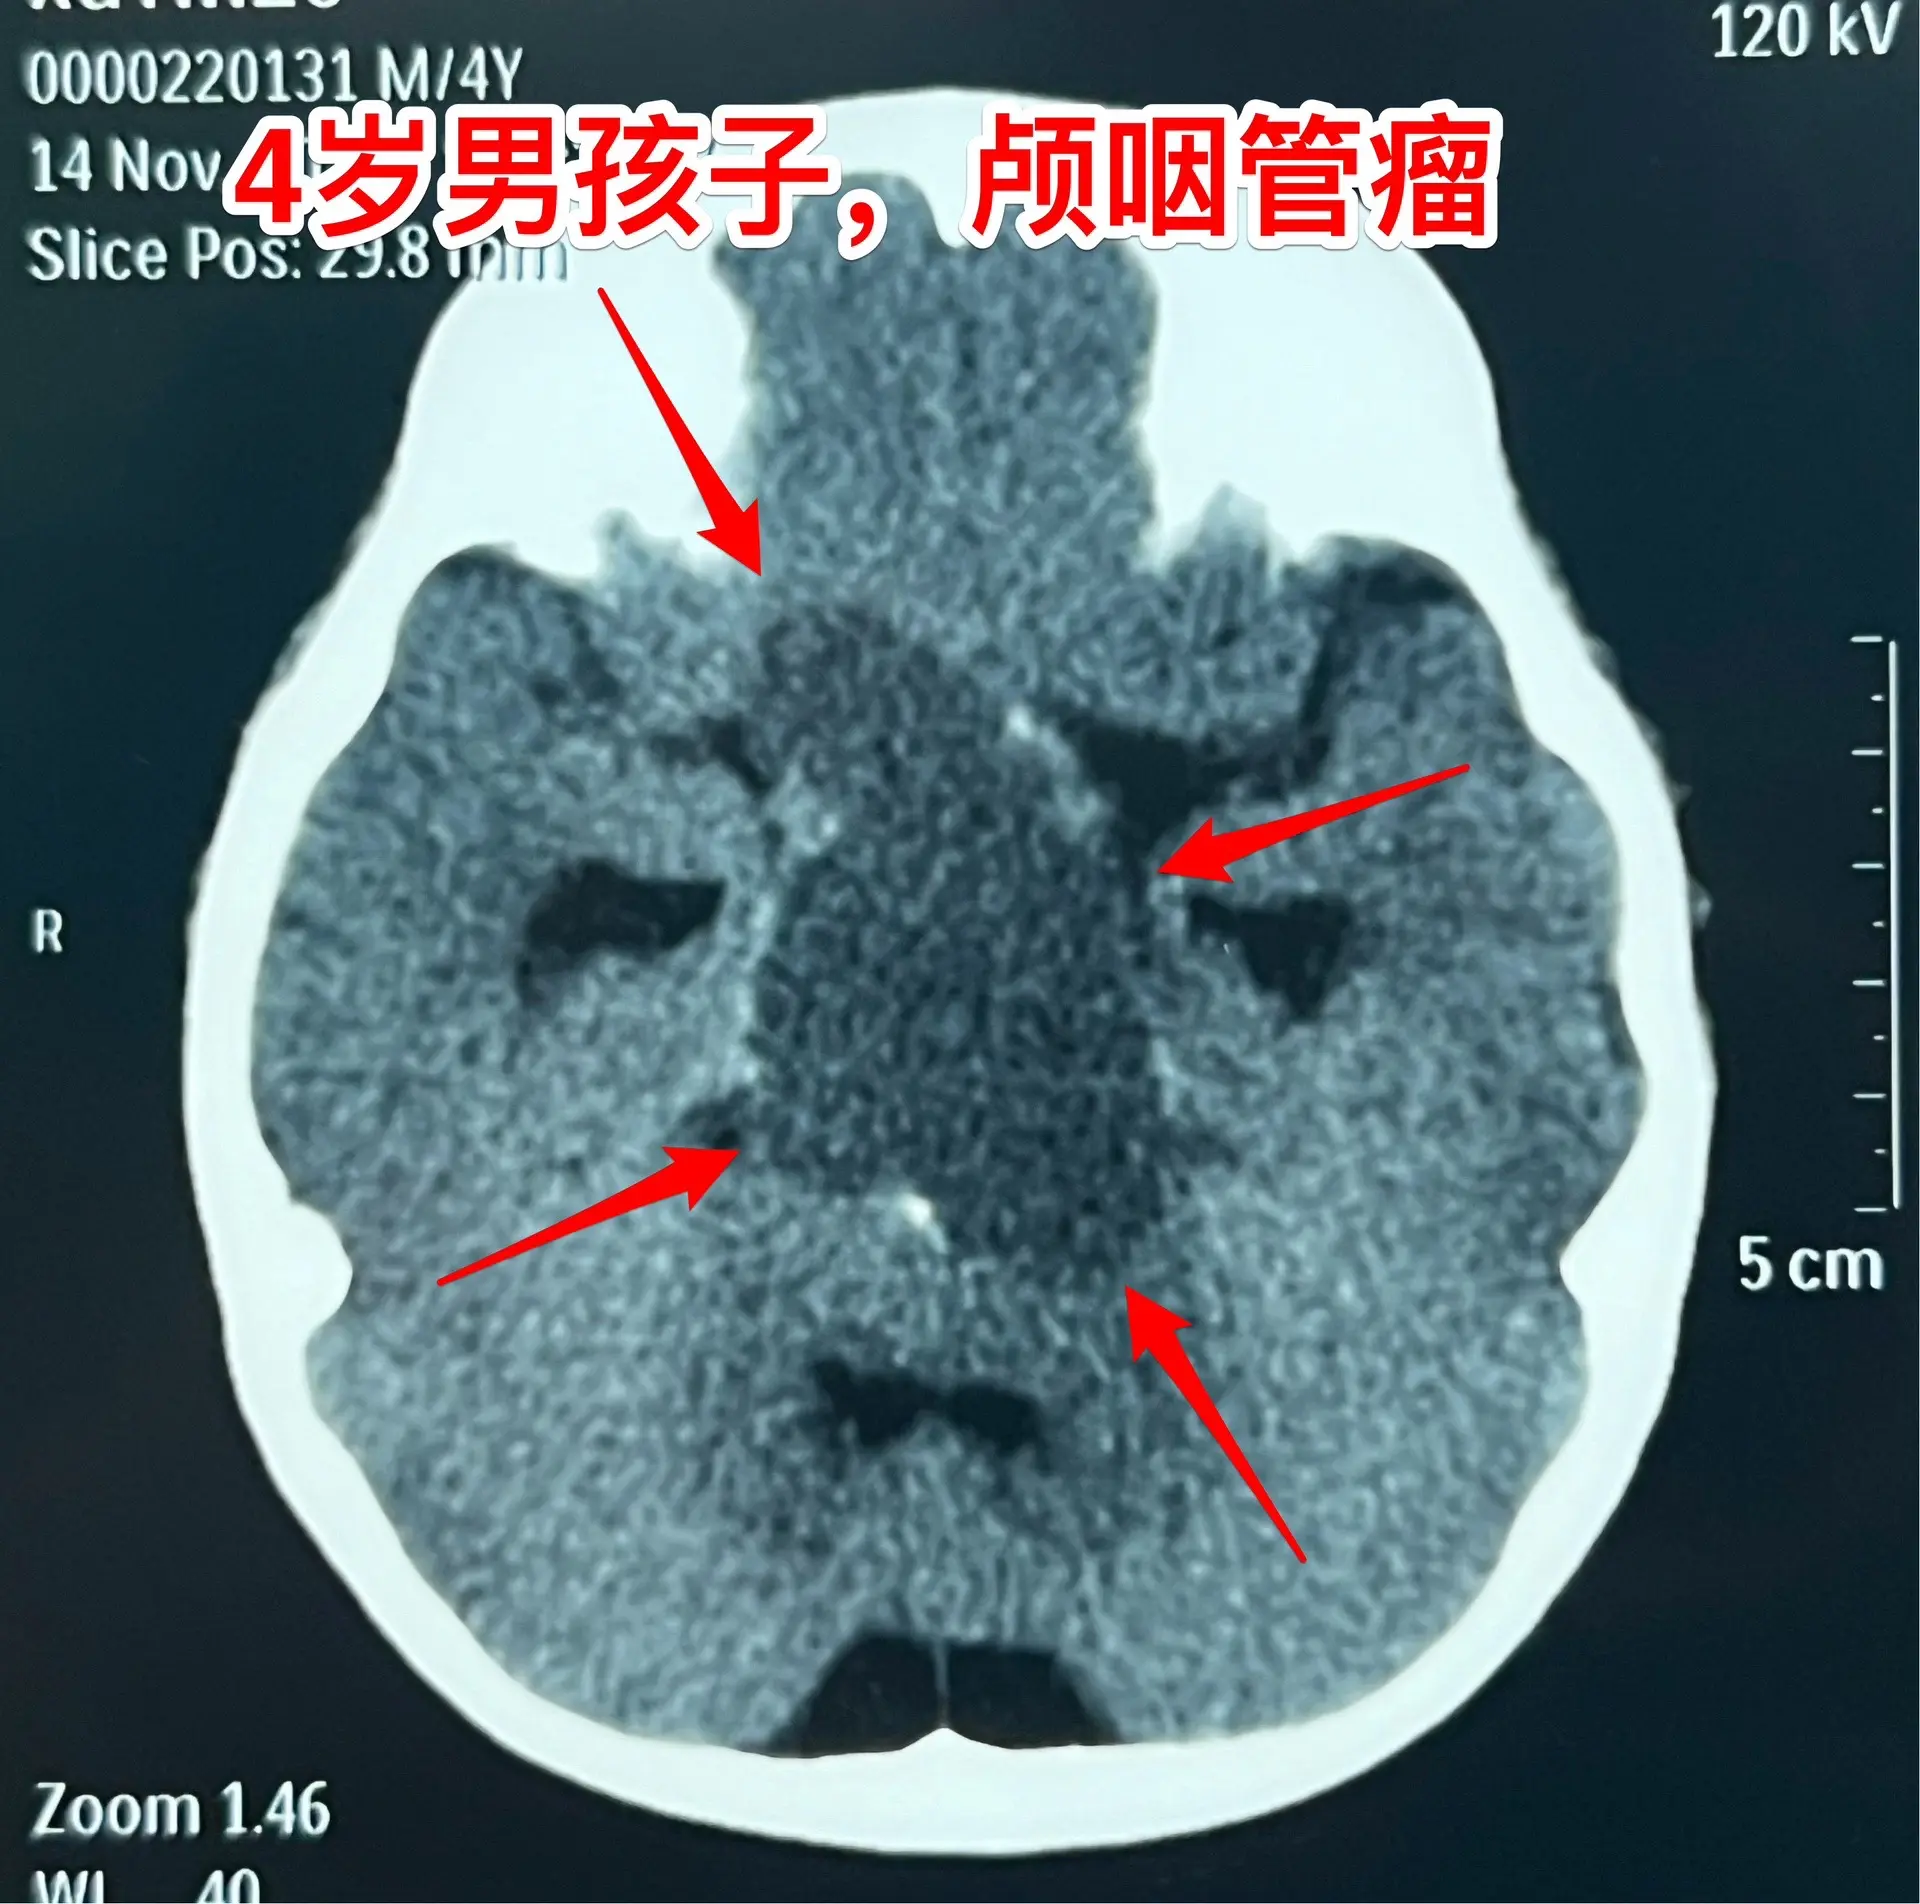

四岁男孩子右侧上下肢有点偏瘫症状!四岁苏州市男孩子出现视力下降、左侧眼睑下垂,伴有右侧上下肢活动力弱。一开始并未发现他的问题,直到右侧上下肢有点儿偏瘫症状才作了脑部CT,发现了颅咽管瘤。 这是典型的颅咽管瘤,囊性伴有钙化。肿瘤压迫视神经和中脑,导致了现有的症状。左侧瞳孔散大、左侧眼睑下垂了,曾经在外院当成了“脑疝”。 在今天(11.17)的手术中发现肿瘤起源于右侧垂体柄-漏斗交界区,是囊性的,抽出囊液是浅黄色的,肿瘤呈外生性生长。肿瘤得到切除,垂体-垂体柄-下丘脑结构得以保护,未来下丘脑-垂体功能值得期待。这样的颅咽管瘤并不多见! 手术结束后三个多小时患儿就清醒了,作了头CT未见肿瘤残留迹象。今晚就从ICU转回了普通病房。